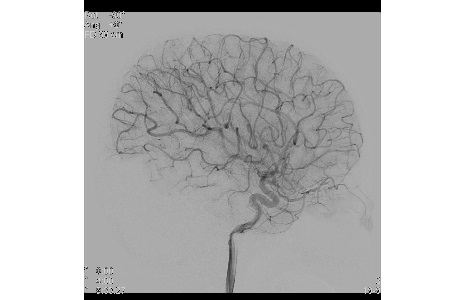

To cope with these challenges Philips’ NeuroSuite consists of a bi-plane interventional X-ray system with a unique combination of two new detectors: Philips’ frontal FD20 detector delivers live 2D and 3D imaging to provide live navigation and immediate therapy feedback. The smaller, lateral FD15 detector can be positioned beyond the shoulders and very close to the head. This shorter distance and unique combination of detectors provides sharp, full brain imaging at lower X-ray dose and 3D imaging optimized for neuro and spine interventions.

“In interventional neuroradiology the performance of the angiographic system is crucial to patient safety,” says Dr Michael Söderman, Associate Professor and Chief of Neuroangiography and Stereotaxy, Department of Neuroradiology, Karolinska University Hospital. “Philips’ latest innovation is NeuroSuite with a new 20 inch detector on the frontal plane, providing superb 3D-images and big enough for spine imaging. On the lateral plane, the new 15 inch detector brings visualization of the complete cerebral vasculature, with reduced collision risks and enhanced projection freedom.”

At the heart of NeuroSuite is Philips AlluraClarity, lowering radiation dose by as much as 73 percent without compromising image quality ² ³: and VasoCT that visualizes intracranial devices in vessel context and vessel morphology down to perforator vessels¹.